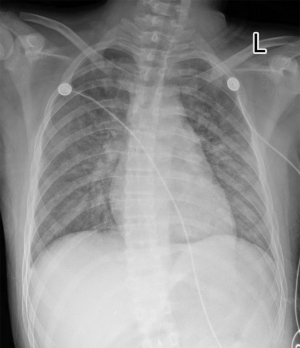

The results of electrocardiogram (ECG) on admission (Figure 1) showed the following: sinus rhythm; atrial premature beat; some lead ST-T segments change (ST segments I, II, III, AVF, and V2–V6 segments depressed, AVR elevated) (A, augmented; V, voltage; R, right arms; L, left arms; F, foot). The X-ray results (Figure 2) showed that the textures of both lungs were increased and blurred, and the heart shadow was slightly larger. No obvious abnormality was found in cardiac ultrasound in our hospital.